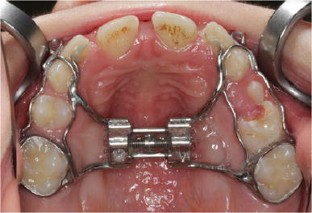

Fig. 1